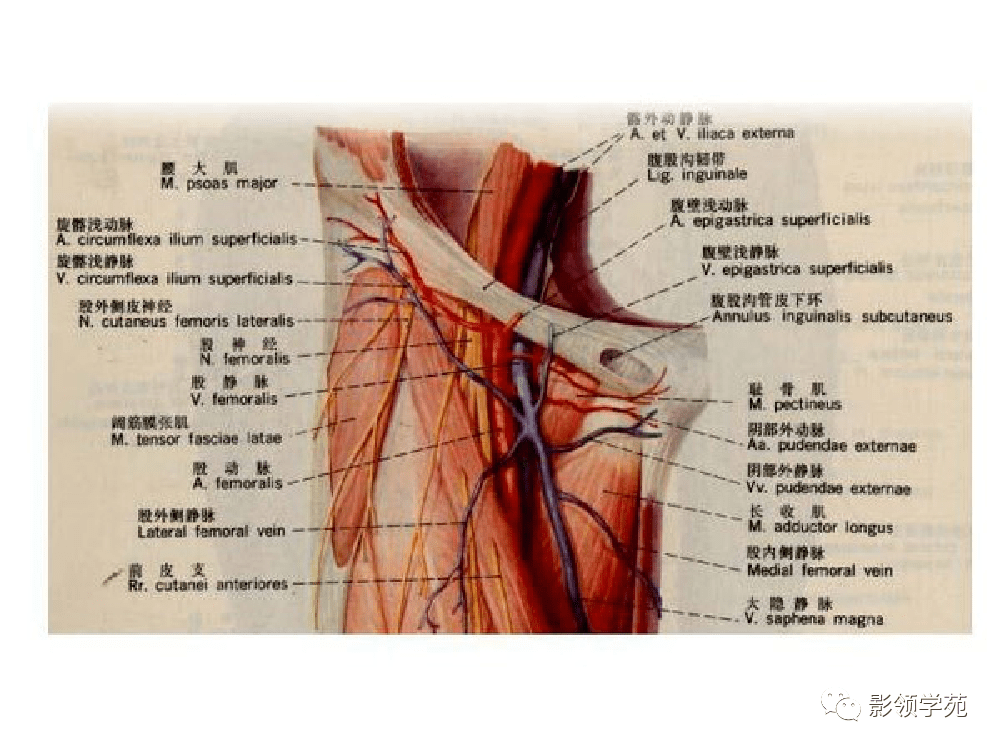

腹部动静脉

腹部动静脉